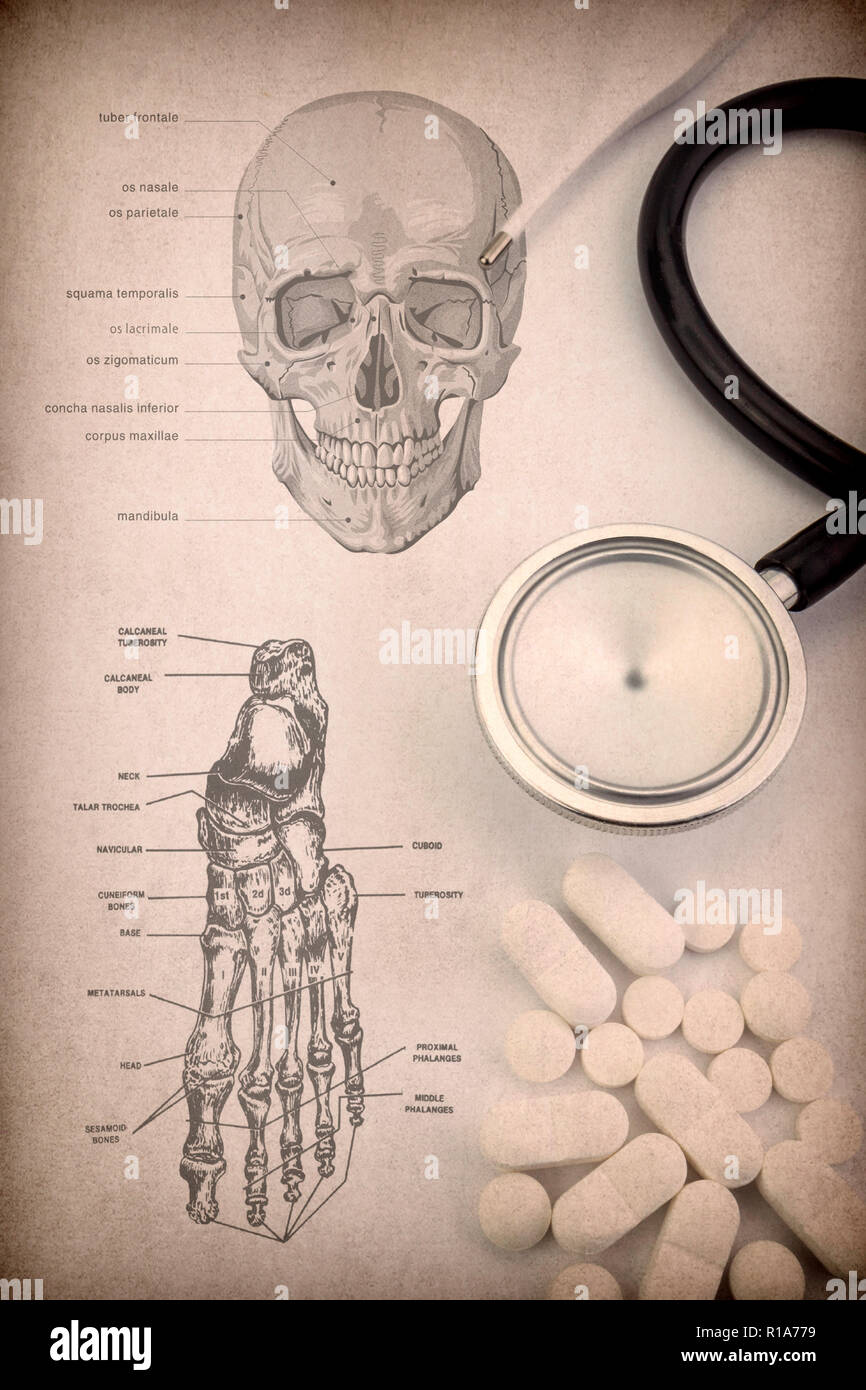

RFR1A779–Squelette humain système détail de tête et pied, pilules, thermomètre et stéthoscope, conceptual image